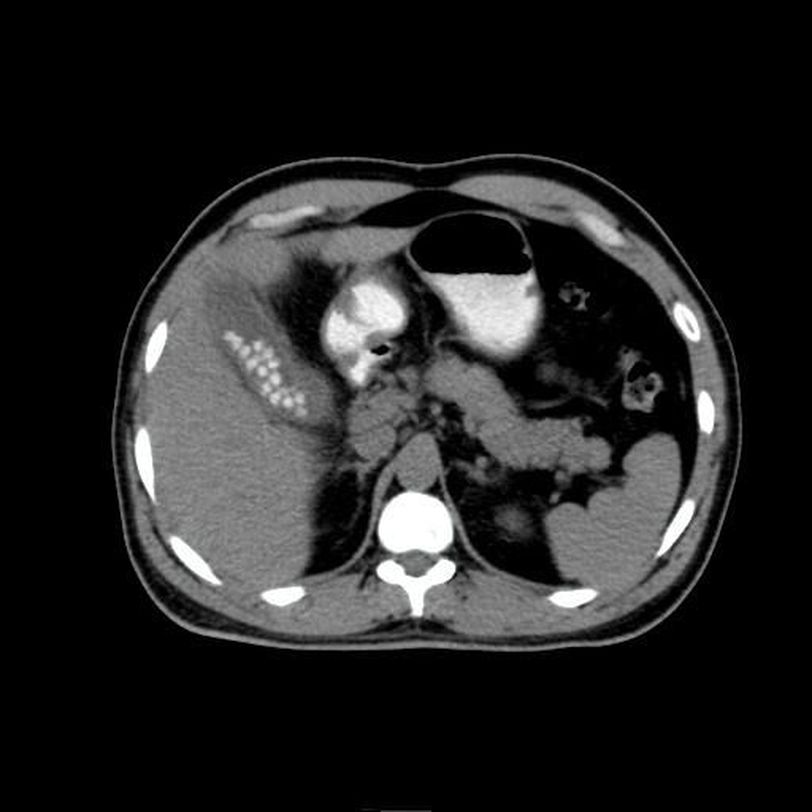

Acute calculus cholecystitis

Acute

Cholecystitis

Calculi